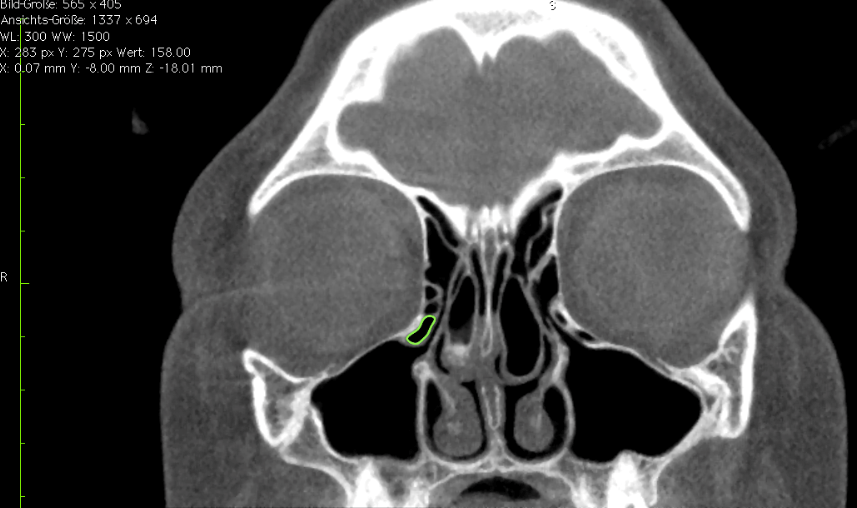

First, the coronal planes were assessed, as this is a common approach in most published studies [36] (Figure 1 [Fig. 1]). In a second step we inspected the axial and sagittal plane to differentiate Haller cells from simple bone crests. Bone crests often mimic complete cells when only viewed in one plane or in summarized two-dimensional radiographs (Figure 2 [Fig. 2], Figure 3 [Fig. 3]).

Figure 1: Bilateral Haller cells on coronal plane of CBCT

Figure 2: Simple bone crests mimicking Haller cell in coronal plane on the left side. The crest is clearly identified on further planes perpendicular to the coronal aspect.